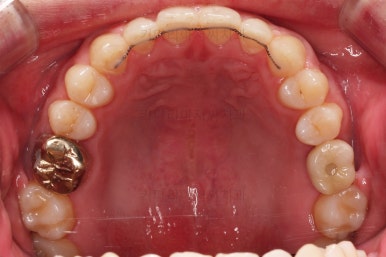

교정장치를 부착하고 충치치료는 별개로 진행되었어요.

이번에 선택하신 장치는 자가결찰(철사를 잡아주는 뚜껑이 자체적으로 달려있는) 메탈(금속)장치이며 엠파워 메탈이라고 하는 장치입니다.

세라믹에 비해 많이 보인다는 단점이 있지만 저렴하고 튼튼한 관리가 약간은 더 편하다는 장점이 있어요.

틈새는 서서히 조여서 없애주고요.

충치치료가 완료된 부위는 골드 크라운(금니)이 씌워졌어요.

임플란트를 하기에 적절한 사이즈로 공간은 맞춰줍니다.